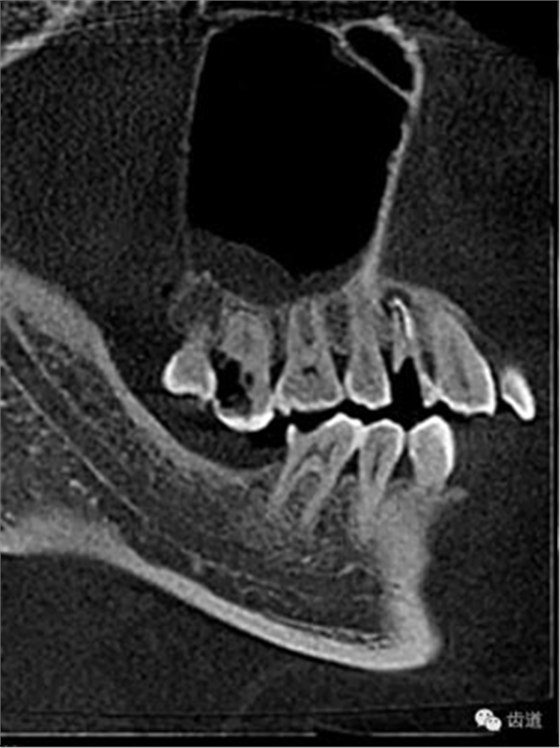

處理:1.建議CBCT檢查。

好的開(kāi)始就是成功的一半。通過(guò)CBCT了解根管的位置,形態(tài),方向。

檢查顯示:近頰及腭根充填恰填,遠(yuǎn)頰根管內(nèi)有少許充填物影像。根尖明顯低密度影像。